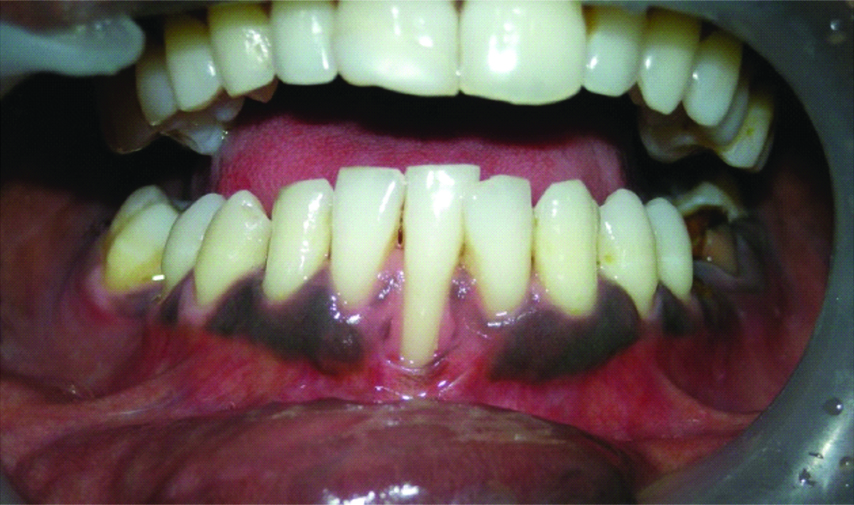

On clinical examination, the patient had the full complement of permanent teeth except for #31 which was congenitally missing. Oral hygiene was fair with mild calculus on the lingual surface of lower anterior teeth. Periodontal examination of the area of complaint showed Miller’s Class III gingival recession in relation to #41 with Clinical Attachment Loss (CAL) of 9 mm, Probing Pocket Depth (PPD) of 2 mm, Recession Height (RH) of 7 mm and Width (RW) at cervical region was 5 mm, at mid and apical region was 4 mm respectively, and the Width of Keratinised Tissue (WKT) was about 1mm [Table/Fig-1,2]. Additionally, there was CAL of 2 mm seen in relation to #44 and #45 which could be due to improper brushing technique by the patient. Hence, it was diagnosed as a case of chronic localised periodontitis in relation to #41.

Preoperative photograph showing Miller’s class III gingival recession in relation to #41.